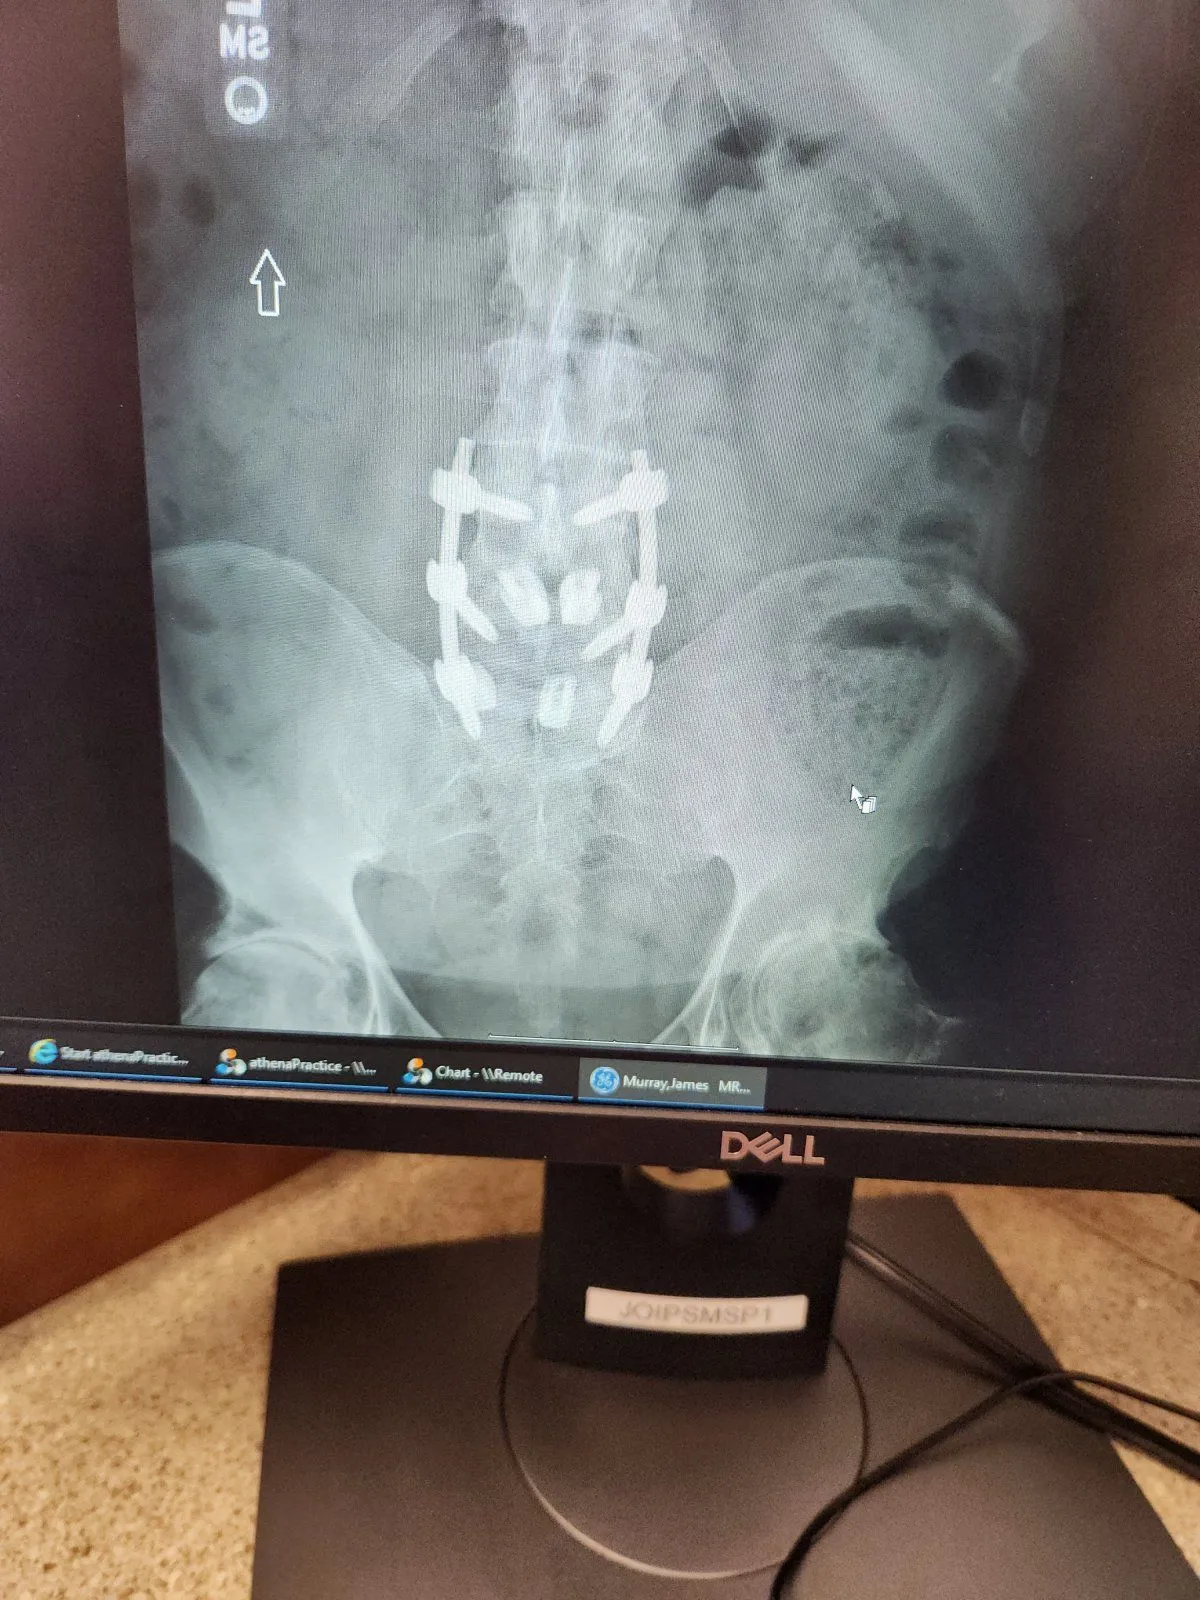

I went to see the doctor back in June 2022, because i was having sciatic nerve pain running down my right side, also which i had been seeing a Chiropractor for over a year. They needed to give me shots to locate what disk was causing the problem, even after i told them that my L5 disk was taken out and it was supposed to fuse. So for the next 6 months they tested, gave shots, Xray, MRI, CTscan, and finally in Dec 2022 i went under the knife. Here are a couple of pics of the end result. I no longer have pain running down my leg, but some stiffness at the operation site, which is to be expected after 1 month. I have titanium cage around the L3,L4,L5 area with screws holding it in place. It took 5 hours(doc predicted 3) to complete the operation.

Back .jpg

side.jpg

That is the big fix you are looking at. No more pain running down the leg, lots of time to heal though. I wanted to get it done back in June but Hospitals must milk the system before they do the final remedy.